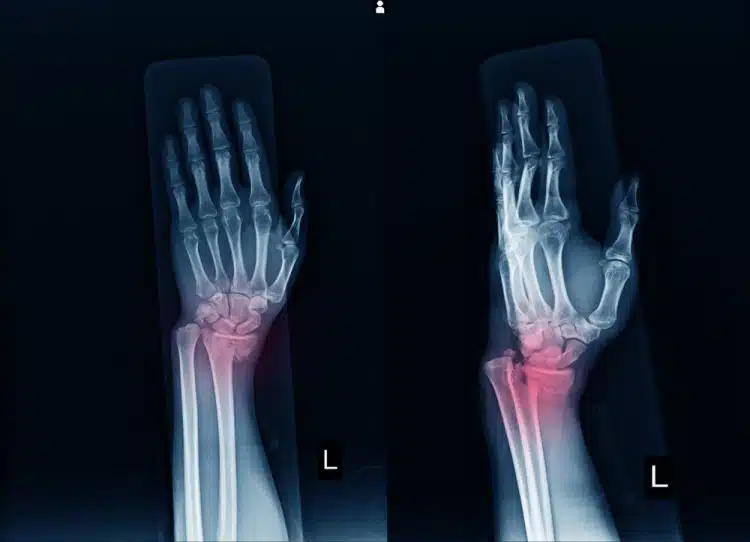

منطقة اليد تكون مهمة للغاية لكونها تساعد الفرد على إتمام الكثير من الأمور والتحرك بحرية وبشكل جيد، ويكون هذا الجزء مرناً نظراً لأن تلك المنطقة تحتوي على ثمانية عظميات صغيرة تعمل على تكوين الرسغ وتكون مرتبطة مع بعضها البعض وتعمل على وصل اليد بالذراع، والعظمة الزورقية تعتبر واحدة من أهم تلك العظميات وتظهر خلال الفحص بالأشعة السينية على شكل زورق.

تكون تلك العظمة في الجهة الخارجية من الرسغ وتعتبر أكثر عرضة للتعرض للكسر من غيرها لكونها تحتل مساحة كبيرة من منطقة الرسغ، ورغم كون مكانها حساس ومهم للغاية فإن عملية وصول الدم إليها تكون معقدة للغاية وتتم من خلال شرايين دقيقة تخرج من تلك العظمة، وترجع الخطورة في مثل تلك الإصابات إلى تعرض تلك الشرايين لضرر نتيجة لكسور أو اصطدام وهذا يحدث الكثير من المضاعفات على المدى البعيد لكون علاجها أمر غير سهل على الإطلاق.

- يطلب بعد ذلك من المريض أن يخضع لفحص بالأشعة السينية لمعرفة حجم الكسر الموجود في العظمة الزورقية وما إذا كانت هناك أية إصابات أخرى في المناطق المحيطة.